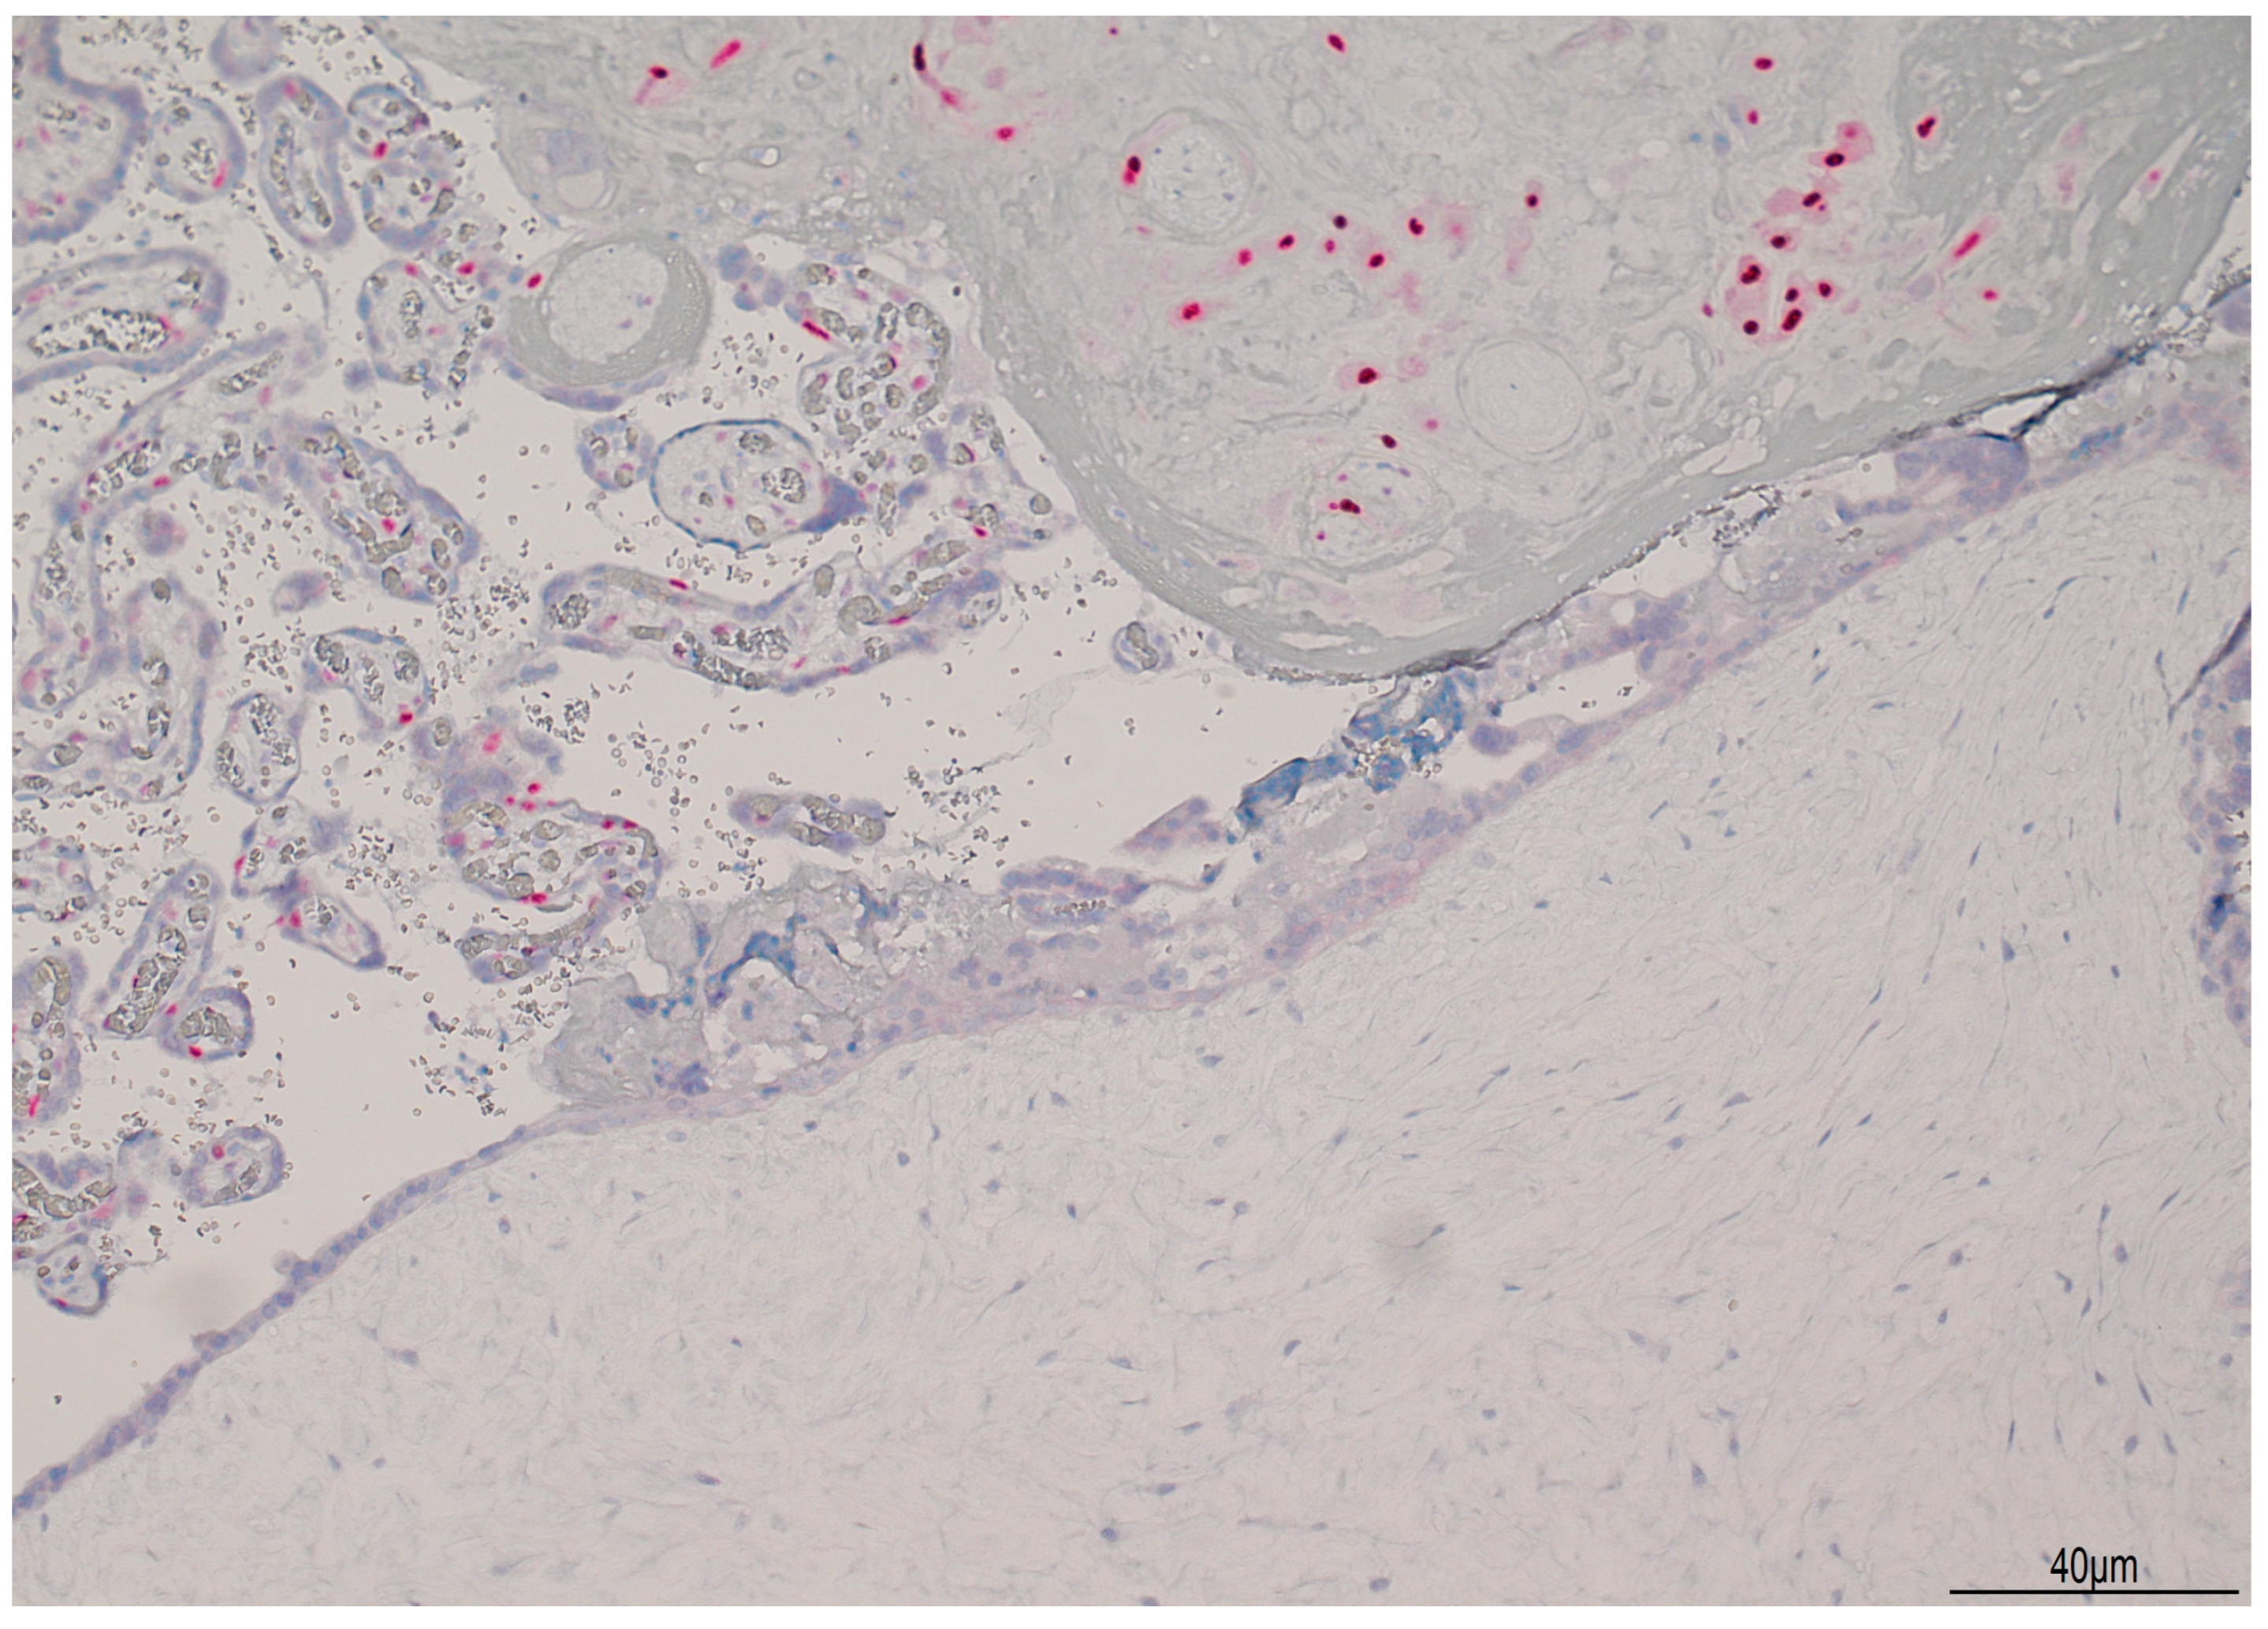

Histologically, the placenta showed a regular villous maturation for 38 weeks of gestational age. The hydropic component showed enlarged and vacuolated villi with well-formed cisterns. The villous trophoblast was circumferentially hyperplastic with atypia involving both cytotrophoblasts and syncytiotrophoblasts (Figure 4). Immunohistochemistry for p57KIP2 was negative in the hydropic component (Figure 5), indicating a CHMCF.

Figure 5.

Immunohistochemistry for p57KIP2: in the molar component, p57KIP2 was negative (lower side of the image), but it was positive in the cytotrophoblast of the normal villi and in the intermediate trophoblast (upper part of the picture).

Differential diagnosis between PHMCF and CHMCF is important as the latter carries a higher risk of maternal complications and progression to GTN. Post-molar GTN may occur in 15–20% cases of CHM, reducing to 1.5% in case of PHM [24]. US is the gold standard in detecting molar degeneration and the diagnosis can be made around the 12–14th week. In CHM, the placenta presents numerous cysts (the “snowstorm” or “clusters of grapes”) and the gestational sac is enlarged with no embryo. In PHM, the increased placental echogenicity is more scattered due to focal hydropic degeneration [25]. Beta-hCG levels are necessary to make the diagnosis of mole, but they do not discriminate between CHF and PHM. Thus, the correct diagnosis is made postnatally integrating US and pathological examination [21]. Morphology and p57KIP2 immunohistochemistry are still time- and cost-effective tools in differential diagnosis. In CHM, nuclear positivity of p57KIP2 is present only in the intermediate trophoblast and in the decidua, but its expression is absent in the villous cytotrophoblast. Instead, in PHM, p57KIP2 is strongly positive in the cytotrophoblast nuclei, other than the other sites aforementioned [7]. Immunohistochemical expression of p57 can be explained as the p57KIP2 gene, a cyclin-dependent kinase inhibitor, located on chromosome 11p15.5, is subject to strong paternal imprinting and is expressed from the maternal allele. As CHM is mostly paternally derived and lacks a maternal genome, p57KIP2 is absent in the villous cytotrophoblast and in stromal cells. On the other hand, in PHM, as it contains maternal DNA, p57KIP2 is instead positive. In both type of moles, hydropic abortion, and in normal pregnancy, p57KIP2 is always positive in the decidua and extra-villous trophoblast. Syncytiotrophoblast cells are always negative [26]. Molecular genotyping can be helpful in differentiating between androgenetic and biparental complete mole, and also in identifying germline mutations in NLRP7 and KHDC3L genes, responsible for recurrent mole [2].

In the case we described, US detection of CHMCF was made early in gestation, at 13 weeks. Placental examination confirmed the US diagnosis, both grossly and microscopically. The enlarged, hydropic villi were adjacent to a normal placenta. Histologically, the typical cisterns with circumferential trophoblast hyperplasia were seen and immunohistochemistry for p57KIP2 was negative in the cytotrophoblast and stromal cells.